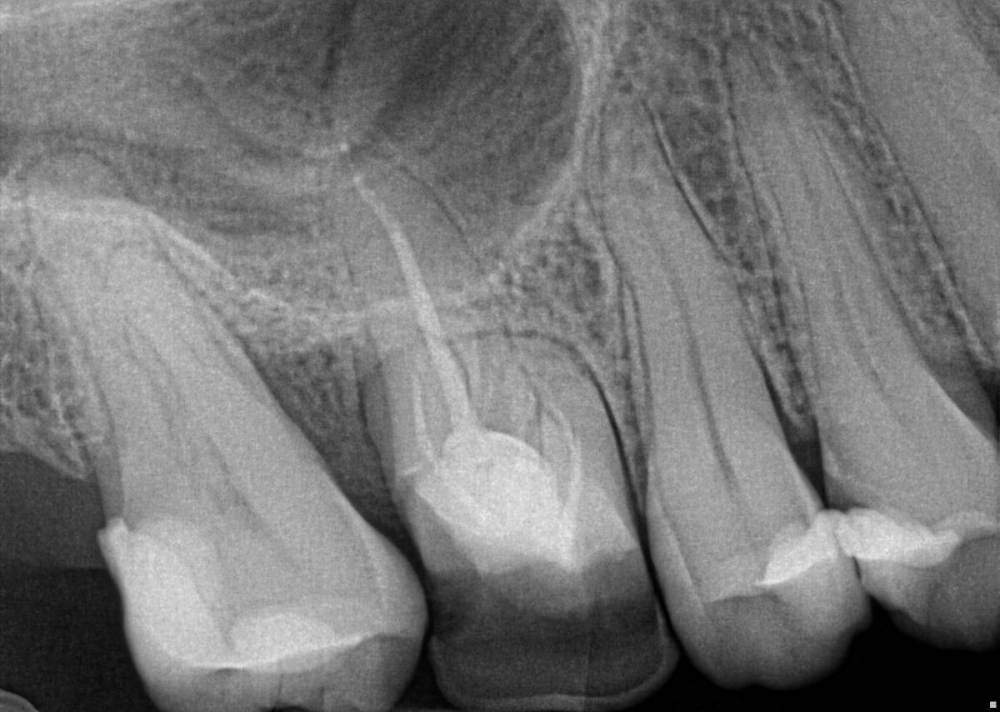

elenaterra Опубликовано 22 декабря, 2021 Поделиться Опубликовано 22 декабря, 2021 (изменено) Проживаю в США в Лос Анджелесе, перед отъездом полечила все зубы, так как знала что здесь очень дорого, да и доверяю только своему стоматологу, к которой хожу лет 20. Так вот где то год назад на нижнем моляре (крупный самый жевательный) снизу слева выпала пломба и там была дыра. Так как денег не было и была депрессия, апатия, зуб не болел и не знала куда идти, я прокрастинировала. Начал он болеть месяц назад, потом прошел, знаю что надо было сразу бежать лечить, но уже есть как есть. В общем он ныл только когда в дырке еда оставалась, я зубочисткой чистила и вроде ок опять. Позавчера поела еду, которую обычно не ем (орехи, каша какая то смесь всего). Ну и начал интенсивно болеть, боль терпимая, но уже на грани. Помогает раствор соль плюс сода. Оформила кредитку местную на лечение, но она все равно не покроет и половину лечения. В одну клинику сегодня позвонила, вроде бы хорошие отзывы, 125 баксов прием первичный посмотреть, они перенаправили к специалисту по Рут каналам из другой клиники. Я позвонила, стоимость Рут канала 1700 это без пломбы, пломбу потом в другой клинике делать. Прием посмотреть 150 долларов. Рассрочки нет никакой у них. Позвонила в другую тоже очень хорошую по отзывам, оказалась можно приехать прямо сейчас. Они сделали три снимка ( у меня ещё две пломбы выпали, но не болят пока что). По итогу несколько зубов удалять, импланты ставить, другую половину коронки и всякий кариес по мелочи. Воспаление мелкое она сказала, вроде как организм мой борется, она так сказала. Этот зуб который болит сказала удалять, я просила Рут канал, сказала очень маленькие шансы на успех и выйдет в тысячи долларов и кучу времени, зато можно вырвать за 500 и поставить имплант и будет как новый (так и сказала). Клиника одна из лучших, отзывы почти все хорошие. Также нашла кусок инструмента который якобы мой стоматолог оставила в другом зубе. Я спросила это точно кусок инструмента (так как своей доверяю и она инструменты не оставляет и после всегда делает снимок), она надо все раскрыть и посмотреть, скорее всего да, вроде как не уверена. Мой вопрос можно ли сохранить зуб или хотя бы попытаться или врач права и только вырывать? Снимок прикрепляю. Ps если можно сохранить, думаю лететь домой, так как здесь у меня вообще доверия не вызвало ничего, даже бахил у них нет, страшно было Изменено 22 декабря, 2021 пользователем elenaterra Ссылка на комментарий

Notherbrick Опубликовано 22 декабря, 2021 Поделиться Опубликовано 22 декабря, 2021 (изменено) Не удаляйте. Судя по снимку зуб более чем имеет шансы и право на жизнь. Изменено 22 декабря, 2021 пользователем Notherbrick 1 Ссылка на комментарий

Pavel-Pskov Опубликовано 22 декабря, 2021 Поделиться Опубликовано 22 декабря, 2021 Цитата Не удаляйте. Судя по снимку зуб более чем имеет шансы и право на жизнь. А нечего, что там дистально кариес корня и похоже, что карман ниже середины корня? 1 2 Ссылка на комментарий

Bier Опубликовано 22 декабря, 2021 Поделиться Опубликовано 22 декабря, 2021 25 минут назад, Pavel-Pskov сказал: А нечего, что там дистально кариес корня и похоже, что карман ниже середины корня? согласен. Возможно и на удаление зуб. Ссылка на комментарий